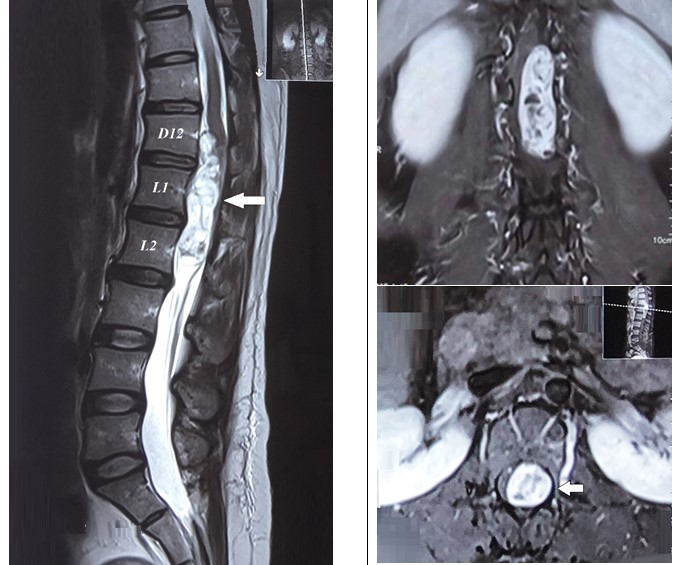

Hình 1. Cộng hưởng từ (hình trái) mặt phẳng cắt dọc cho thấy một khối kích thước ## 67x21x18mm trong màng cứng, ngoài tủy được giới hạn rõ gây chèn ép lên vùng chóp tại D12 – L2. (Hình phải) mặt phẳng cắt ngang khối u tăng tín hiệu trên T2, với sự tăng cản quang đồng nhất sau khi tiêm gadolinium (mũi tên).

Hình ảnh cộng hưởng từ cho thấy một khối lớn trong màng cứng, ngoài tủy chèn ép vào vùng tủy sống tại đốt sống D12 – L2, kích thước # 67x21x18mm. Khối có tín hiệu thấp trong mô tủy trên T1 và có tín hiệu hơi cao trên T2, với sự tăng cản quang sau khi tiêm gadolinium. Giới hạn khối u rõ và chiếm gần hết ống sống về phía sau và trái mà không có sự phá hủy xương hoặc xâm lấn màng cứng cũng như tủy, Bệnh nhân được chẩn đoán theo dõi u schwannoma đoạn thắt lưng cùng và chỉ định phẫu thuật bóc u vi phẫu. Bệnh nhân được phẫu thuật ngày 28/3/2021, Phẫu thuật viên: BSCKII. Nguyễn Thanh Minh, ThS. Đinh Thị Phương Hoài, BSNT. Dương Đức Anh.